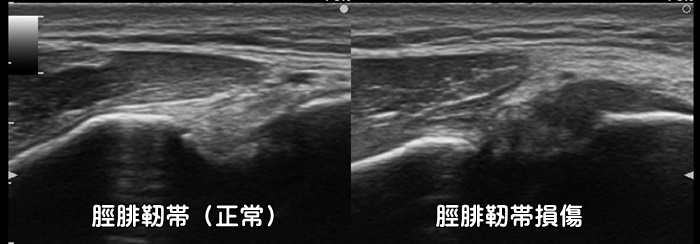

脛腓靭帯損傷

一般的な足首の捻挫として見逃され、なかなか治癒しない比較的稀な靭帯損傷です。詳細な圧痛の部位や脛腓靭帯損傷を疑った徒手検査を行う事で診断はつきますが、エコーでは損傷や炎症の程度が確認可能です。但し脛腓靭帯損傷では骨折を合併している事も多い為注意が必要です。